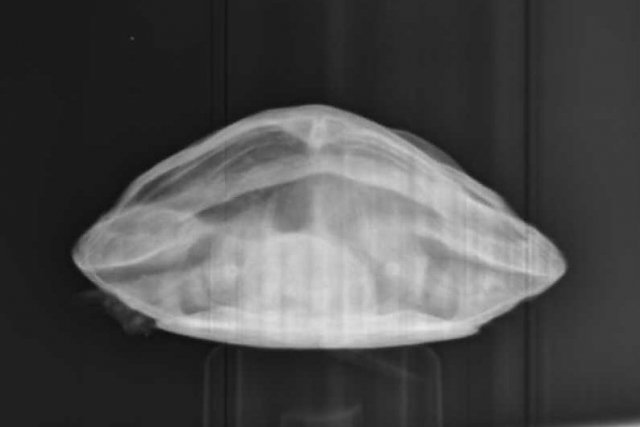

Алексей Alex-Raduga Ваше имя: Алексей Локация: Россия, МО, Серпуховский район Опубликовано: 31 января 2024 Автор Опубликовано: 31 января 2024 @moth здравствуйте ! Сегодня возил на рентген, сделали все проекции, Савина сказала - возможно пневмония, назначила антибиотик энрофлоксацин 2,5%, по 0,12мл 3-4 раза через день и элеовит 0,18мл. - 2 раза с интервалом в 14 дней. Также остается эспусмизан еще 14-21 день (21 день уже его давал, с кормом раз в 3 дня). Также назначила взять анализ кала. Если не пройдет - сказала везти на КТ. Все верно, больше ничего пока не нужно ?

Консультанты moth Ваше имя: Мария Локация: Москва Опубликовано: 31 января 2024 Консультанты Опубликовано: 31 января 2024 @Алексей Alex-Raduga да, всё верно одно лёгкое мутное совсем, жалко тогда она не стала другие проекции делать. А Элеовит ему делали раньше?

Консультанты moth Ваше имя: Мария Локация: Москва Опубликовано: 8 февраля 2024 Консультанты Опубликовано: 8 февраля 2024 @Алексей Alex-Raduga она сказала, что тут однозначно кт нужно. Либо лёгкое схлопнулось, либо сильная односторонняя пневмония. Трава с мостика такое бы не вызвала.

Алексей Alex-Raduga Ваше имя: Алексей Локация: Россия, МО, Серпуховский район Опубликовано: 15 февраля 2024 Автор Опубликовано: 15 февраля 2024 (изменено) Результаты Кт : Протокол КТ Информация по животному Тотоша ,рептилия ,Черепаха красноухая. Протокол ДЫХАТЕЛЬНЫЕ ПУТИ - Визуализируется короткая трахея, разделяющаяся на два бронха, делающие изгиб в дорсальном направлении и входящие в легкие. Правое легкое имеет типичный сегментированный многокамерный вид, пневматизировано, имеет ретикулярный и "сотовый" рисунок, определяется умеренное утолщение перегородок. Бронх левого легкого частично пневматизирован, на остальном протяжении заполнен мягкотканым патологическим содержимым. Левое легкое уменьшено (25х16х12 мм), безвоздушно, паренхима уплотнена до мягкотканых значений, перфузия сохранена, слабо неравномерная. КОСТНЫЕ СТРУКТУРЫ - без патологических изменений. СЕРДЦЕ - без патологических изменений. ПЕЧЕНЬ - без патологических изменений. ЖЕЛЧНЫЙ ПУЗЫРЬ - в правой доле печени, грушевидной формы, умеренно наполнен однородным жидкостным содержимым. СЕЛЕЗЕНКА - овальной формы, 12 мм, расположена дорсо-медиально от желудка. ПОДЖЕЛУДОЧНАЯ ЖЕЛЕЗА - не визуализируется. ЖЕЛУДОК - не наполнен, стенки не утолщены. КИШЕЧНИК - содержит минимальное количество химуса и газ, стенки не утолщены. ПОЧКИ - локализованы в дорсальной части каудального целома, структура и перфузия не изменены. МОЧЕВОЙ ПУЗЫРЬ - умеренно наполнен, стенки не изменены. ПОЛОВЫЕ ОРГАНЫ - не визуализируются. Заключение Заключение: КТ-признаки тотальной левосторонней пневмонии. Обструкция левого бронха. Информация по животномуТотоша ,рептилия ,Черепаха красноухая Анамнез: В мире животнрых (Серпухов) Савина Ярослава Игоревна Жалоба - в течении месяца всплывает на одну сторону (правую). Бывли в сторонней клинике - назначили антибиотик, газасвязывающий препарат, витамины. Активность - норма. Аппетит - норма. Дефекация - норма. Кормление - корм для черепах. Содержание - аквариум, вода 26-27 гр, мостик, УФ лампа и лампа нагрева. Объективно: Общее состояние - удовлетворительное на момент осмотра. Ментальный статус - ясный. Дегидратация - не выражена. Глаза - чистые. Носовые ходы - чистые. Ротовая полость - без патологий. ВСО - бледно-розовые. Состояние кожного покрова и панциря - линька. Упитанность - норма. М - 272 гр. Диагнозы: Предварительный диагноз: Пневмония Врач: Ложечко Анастасия Леонидовна А НАЗНАЧЕНИЙ НЕТ ! Чем лечить-то ? Продолжить уколы энрофлоксацина ? Изменено 15 февраля 2024 пользователем Алексей Alex-Raduga